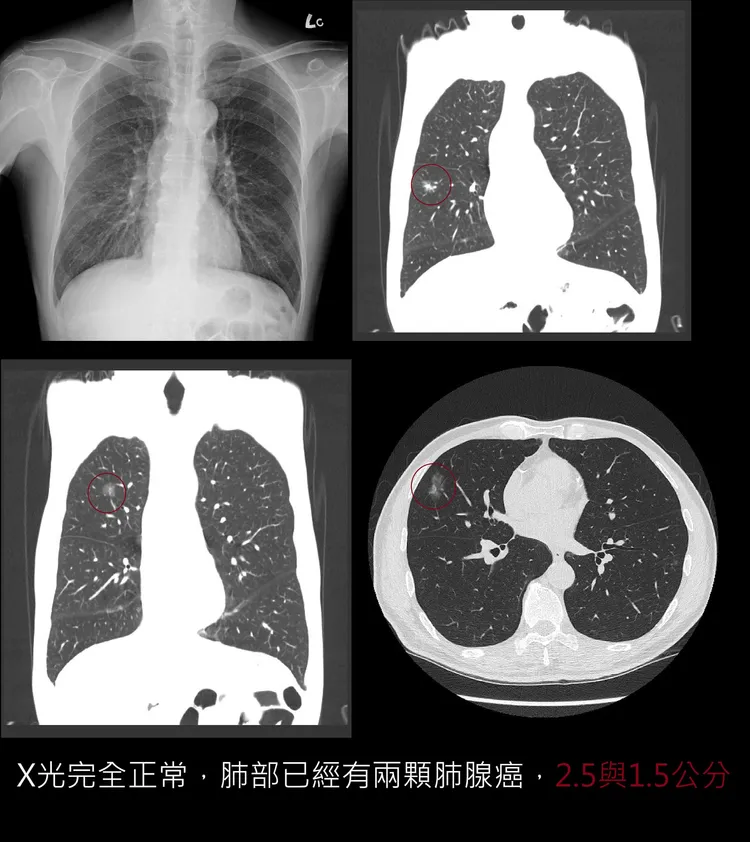

蘇一峰這才明白,原來是這位大哥兩年前,在他的門診就醫時,由於胸腔X光全正常,當時蘇一峰安排做了LDCT低劑量電腦斷層,發現了兩個肺結節一個2.5公分,一個1.5公分!蘇一峰立刻將病患轉診找北榮胸腔外科主任開刀。

這名病患告訴蘇一峰,術後胸外主任告訴他,「兩顆結節開刀開下來都是肺腺癌」,甚至「你再晚半年開刀就來不及了!」之後追蹤兩年沒有復發!病患特地掛號向蘇一峰表達感謝「我今天特別來跟蘇醫師您說謝謝!讓我從死神逃過一劫了!」

最後,蘇一峰提醒,很多肺結節長到兩公分,X光仍然看不見,千萬不要以為 「X光正常就等於沒有肺癌!」